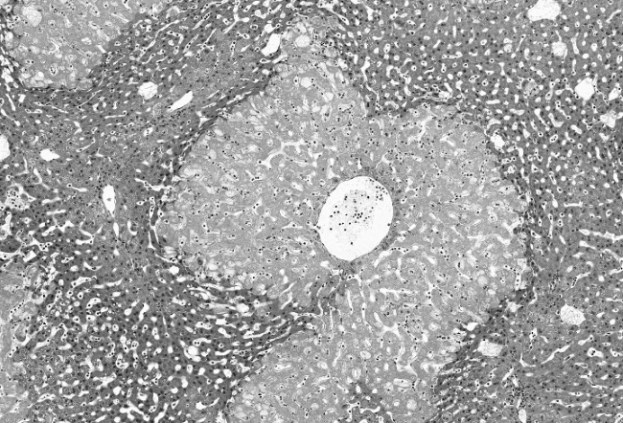

Системы органов С классификацией систем органов ситуация обстоит так же, как и с подсчетом точного количества органов в организме. Эта книга познакомит вас с 10 системами органов: • покровной; • опорно-двигательной; • сердечно-сосудистой; • лимфатической; • дыхательной; • нервной; • эндокринной; • пищеварительной; • половой. Некоторые эксперты считают, что иммунная система не входит в состав лимфатической, а мышечная относится к скелетной. Другие же объединяют лимфатическую, иммунную и сердечно-сосудистую в одну – кровеносную. Абстрагируясь от подобных вариантов, стоит помнить, что системы органов не работают изолированно: в разных системах есть множество перекликающихся функций, из-за чего точность классификации отходит на второй план. ![]() Внутренний баланс Наши системы органов отвечают за поддержание двух взаимосвязанных процессов: метаболизма и гомеостаза. Метаболизм не сводится к скорости, с которой мы перерабатываем пищу, чтобы производить энергию. Метаболизм представляет собой сумму всех химических реакций, происходящих внутри организма. Гомеостаз – это способ, которым организм достигает постоянства внутреннего состояния, вне зависимости от внешних условий. Метаболизм Метаболизм – это больше, чем деление пищи на составные элементы (белки, углеводы и сахара) в процессе, который называют катаболизмом. К метаболизму относится и обратный процесс – анаболизм. Он описывает, как именно организм использует молекулы меньшего размера (амино- и жирные кислоты) для создания более сложных молекул, способных накапливаться в виде энергии или использоваться для различных целей – от роста до борьбы с инфекциями. Скорость данных процессов зависит от различных факторов, включая возраст, пол и наследственность. ![]() Форма активного участка фермента уникальна (напоминает замок). Реакция может происходить, только когда субстрат (ключ) подходит к ферменту (замку). В результате продукты могут соединяться или расщепляться. К эффекторам метаболизма иногда относят ферменты, потому что они являются биологическими катализаторами, ускоряющими химические реакции в клетке. Катализировать реакции этим белкам позволяет их особая шаровидная структура. В ферментах присутствуют щели (или активные центры), в которые попадают «правильные» молекулы (субстраты). Затем эти вещества распадаются (разлагаются) на две составляющие либо соединяются, образуя более крупную молекулу. Ферменты легко узнать по названию – все они пишутся с суффиксом «-аза» (например, полимераза, амилаза и дегидрогеназа). Большинство ферментов находится внутри клетки. Наличие ферментов в крови может указывать на возможное повреждение тканей. Например, лактатдегидрогеназа (ЛДГ) обычно присутствует в клетках печени и сердца, поэтому повышение ее уровня в крови говорит о возможных повреждениях данных органов. Объем вырабатываемых ферментов строго ограничен – во избежание любой реакции (слишком быстрой или медленной), способной пошатнуть баланс веществ в организме и в конечном счете повлиять на гомеостаз. Гомеостаз Гомеостаз – это динамический и автоматический процесс, направленный на достижение внутреннего физиологического покоя. Гомеостаз во многом зависит от обратной связи со стороны различных систем органов, в частности – от нервной и эндокринной систем. Благодаря циклу отрицательной обратной связи наш организм способен управлять реакциями и минимизировать любые дисбалансы. Ведь иначе подобные реакции могут привести к болезни и, в худшем случае, к смерти. Гомеостаз в действии Несколько систем органов отвечает за регуляцию водного обмена в организме. При обезвоживании объем воды в крови падает. Тогда особая мозговая структура – гипоталамус – замечает изменение в состоянии и подает сигнал, который мы воспринимаем как жажду. Далее гипоталамус начинает выделять гормоны, которые заставляют почки экономить воду. Мы пьем воду до тех пор, пока ее уровень в крови не восстановится. После этого гипоталамус регистрирует это новое состояние и начинает постепенно снижать уровень гормонов, посылаемых в почки. Когда клетки умирают Главной особенностью всех живых существ, будь то одноклеточные или многоклеточные, является их гарантированная смерть. Это довольно парадоксальная черта, ведь, с одной стороны, она определяет, что такое быть живым, а с другой – лишний раз подчеркивает факт неизбежной гибели. На клеточном уровне смерть – примечательное событие. Сигнальные пути, отвечающие за эту важную процедуру, так же сложны и разнообразны, как и сама жизнь. Для одноклеточного организма гибель клетки – это рок, обрывающий жизнь. Но у многоклеточных организмов, как мы знаем с начала XX века, смерть клеток играет важную роль в нормальном процессе развития. Исторически мы привыкли рассматривать смерть клетки в зрелом организме как некоего врага жизни, проводя аналогию с часами, замедляющими свой ход из-за пагубных влияний среды. Эта точка зрения потеряла свою актуальность: теперь мы понимаем, что многие травмы, вызванные внешними агентами, способны запускать суицидальную программу и активировать процедуру по избавлению от поврежденных клеток. С адаптационной точки зрения данный процесс является оптимальным решением. С начала 1990-х годов в понимании механизмов клеточной гибели произошел радикальный сдвиг. В результате было выделено два явных сценария: случайная и запрограммированная гибель. ![]() Недостаток кислорода или питательных веществ (или воздействие токсических веществ) может привести к гибели клеток печени из-за некроза. Обратите внимание на их бледную цитоплазму, потерю ядра, тканевую структуру и очаги воспалительных клеток (черные точки).

При некрозе клетки теряют способность управлять транспортом веществ внутри себя. Клетки и органеллы набухают, а затем лопаются, выбрасывая содержимое во внеклеточную жидкость. Случайная гибель клетки: некроз Случайная гибель клеток происходит неожиданно и не имеет четко выраженной цели. Она пагубна для всего организма. Такой сценарий иногда называют патологической гибелью клеток, или некрозом (от греч. nekros – мертвый). Некрозные клетки почти всегда отмирают вследствие острой или тяжелой травмы, вызванной: • экстремальными изменениями в водно-электролитном балансе (электролиты – это соли и минералы); |